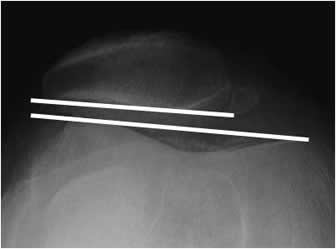

Angulo patelo-femoral:

Trazado por una línea que pasa por el borde externo de la patela y la línea intercondilea. Normalmente se encuentra un ángulo de vértice medial, que se horizontaliza o invierte en caso de desplazamiento lateral y luxación recidivante. (1). (Fig 76 y 77).

Fig 76. Angulo patelofemoral.

Rx tangencial a 30º. Angulo normal, de vértice medial.